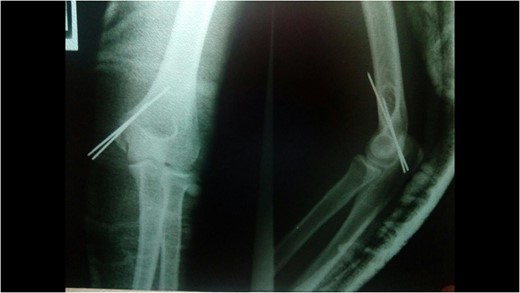

A 14-year-old male patient presented to the emergencies department complaining of intense pain in the left elbow secondary to a fall with an outstretched hand while practicing soccer. He had no significant comorbidities. At physical examination he presented with deformity located on the left elbow, he was unable to passively or actively mobilize it, he reported paresthesias and diminished sensation located on the fifth and fourth digit. X-rays showed a dislocation on the left elbow and an avulsive fracture of the medial epicondyle of the distal humerus (Fig. 1). He was taken to the operating room where a closed manipulation was performed; however the reduction was not achieved due to the interposition of the fractured medial epicondyle. A medial approach to the elbow was performed; intra-operative findings included rupture of the medial capsule and intra-articular interposition of the fragment of the medial epicondyle with a posterolateral dislocation of the elbow, the ulnar nerve showed compressive injuries at the site of the fracture (Fig. 2). Extraction and fixation of the interposed intra-articular fragment was performed followed by elbow reduction and a medial capsule repair, without ulnar nerve transposition (Fig. 3). The patient was left with a posterior splint for a month. After a 3 month follow-up, he has recovered full range of motion of the elbow with recovery of strength and sensation over the distribution of the ulnar nerve.

X-rays showing the result of the first attempt of closed manipulation and open reduction.